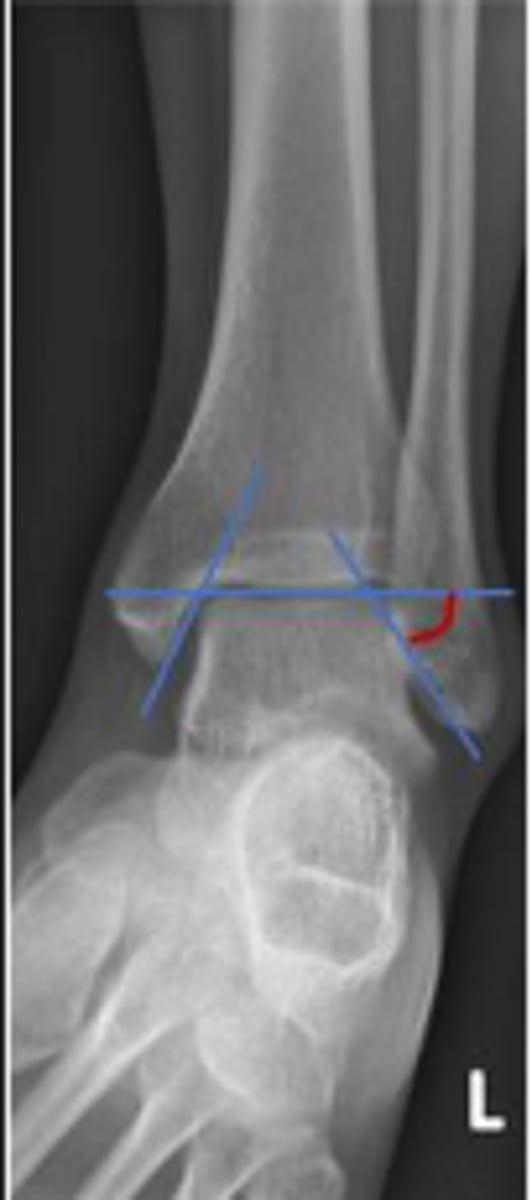

Axial relationship of the ankle

What is the overarching name of the assessment?

Tibial angle & fibular angle

What are the 2 components of the assessment?

Tibial angle

What is the name of the assessment?

Yes

Is the assessment within normal limits?

Fibular angle